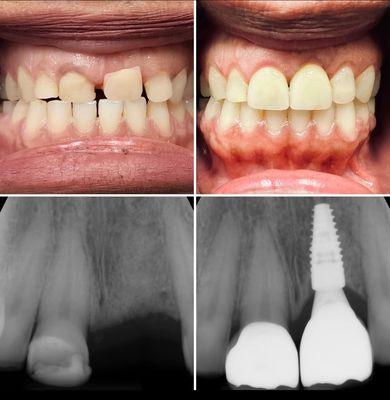

About|Dental Blush is a leading dental clinic in Miami, Florida, dedicated to providing top-notch dental care and improving the health and aesthetics of their patients' smiles. With a team of experienced dentists and state-of-the-art facilities, they offer a wide range of services, including orthodontics, cosmetic dentistry, dental implants, Invisalign, root canal treatment, teeth whitening, and more. Committed to affordability and personalized care, Dental Blush ensures that everyone, regardless of their budget, can enjoy a bright and healthy smile. With a friendly and welcoming atmosphere, Dental Blush strives to make every dental visit comfortable and stress-free. They utilize advanced technology and modern equipment to deliver efficient and pain-free treatments, while their clear pricing policy ensures transparency and eliminates surprises. In addition, Dental Blush offers emergency dental services, providing immediate relief for patients experiencing dental pain or unexpected dental issues. Whether you're looking for general dentistry or specialized treatments, Dental Blush is the go-to dental clinic in Miami for comprehensive and affordable dental care. Generated from the website

About|Doral Dental Studio in Sweetwater, FL is a dedicated dental office that provides high quality and affordable dental care to patients of all ages. Their experienced professional team combines state-of-the-art technology with proven methods of treatment to help patients maintain a healthy and beautiful smile. From routine checkups and cleanings to cosmetic smile makeovers and emergency care, Doral Dental Studio is well-prepared to meet all dental needs with a gentle touch and a focus on patient comfort. With a commitment to treating patients as partners in care, Doral Dental Studio offers tailored treatment plans to achieve optimal oral health and fulfill cosmetic smile goals. Their range of services includes implant dentistry, cosmetic dentistry, all-on-4 dental implants, crowns and caps, emergency dentistry, and laser dentistry. By delivering one-of-a-kind results to one-of-a-kind patients, Doral Dental Studio aims to be the dentist of choice for families in Miami, FL. Generated from the website